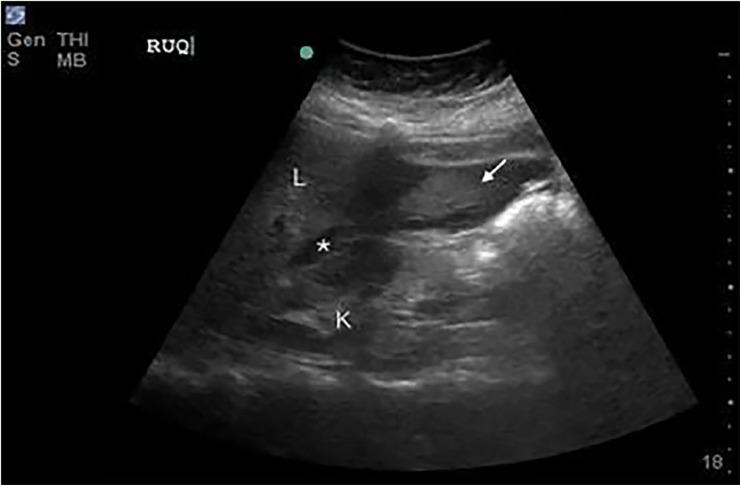

A young woman presented to the emergency department with lethargy, hemodynamic instability, and diffuse abdominal tenderness. On point-of-care ultrasound (PoCUS), she was found to have intraperitoneal free fluid and a large pelvic mass, which were discovered intraoperatively to be hemoperitoneum due to ruptured vessels of a uterine leiomyoma. Although rare, a life-threatening, ruptured leiomyoma may be treated surgically if recognized in an expedient fashion. A PoCUS can aid the emergency clinician in prompt diagnosis.

一名年轻女性因嗜睡、血流动力学不稳定和全腹压痛就诊于急诊科。床旁超声(PoCUS)检查发现她有腹腔内游离液体和一个巨大盆腔肿块,术中发现是子宫平滑肌瘤血管破裂导致的腹腔积血。虽然罕见,但如果能及时识别,危及生命的破裂平滑肌瘤可通过手术治疗。床旁超声可帮助急诊医生进行快速诊断。